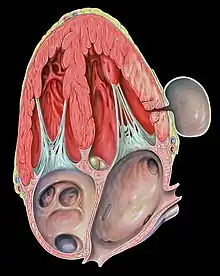

| Pseudoaneurysm of the left ventricle, four-chamber echocardiography view | |

A pseudoaneurysm may also occur in a chamber of the heart following myocardial damage due to ischemia or trauma. A pseudoaneurysm of the left ventricle is a potentially lethal complication of a heart attack.

Although aneurysms and left ventricular aneurysms may involve any wall segment, "aneurysms" in the posterolateral wall are frequently due to pseudoaneurysms. In contrast, the most common location for a true left ventricular aneurysm involves the apex of the heart.